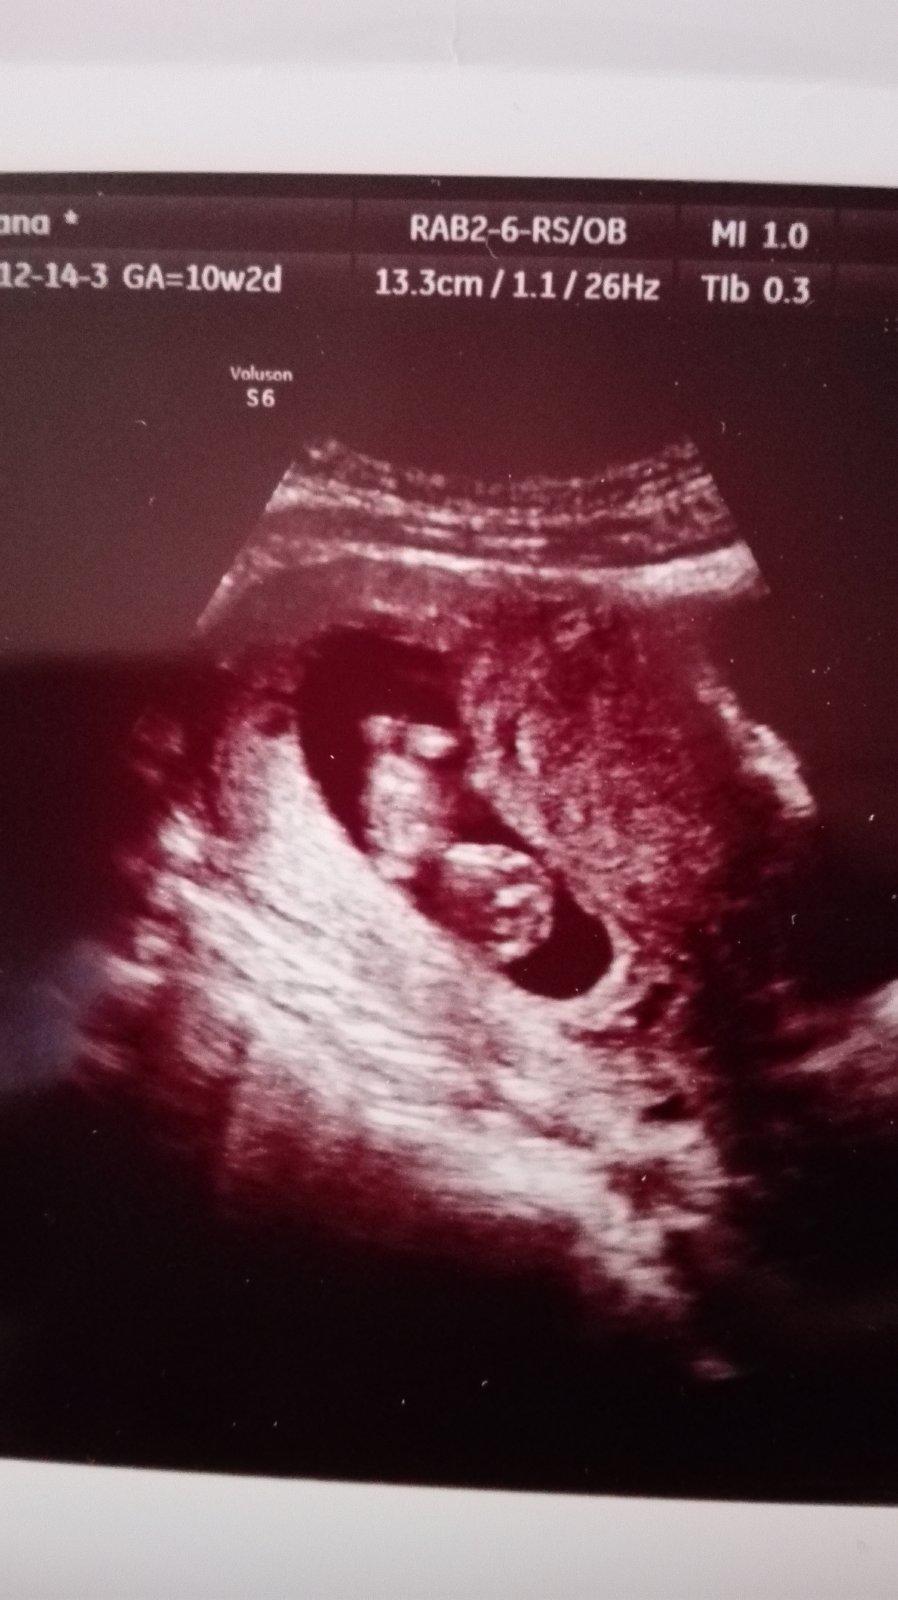

@zuzuliena1 jeeeej bábätko krasne 😍 Gratulujem a kraaaasne tehulkovanie želám 😊

@zuzuliena1 Gratulujem, krásna foto 😍 prajem krásne a zdravé tehu až do konca 😉